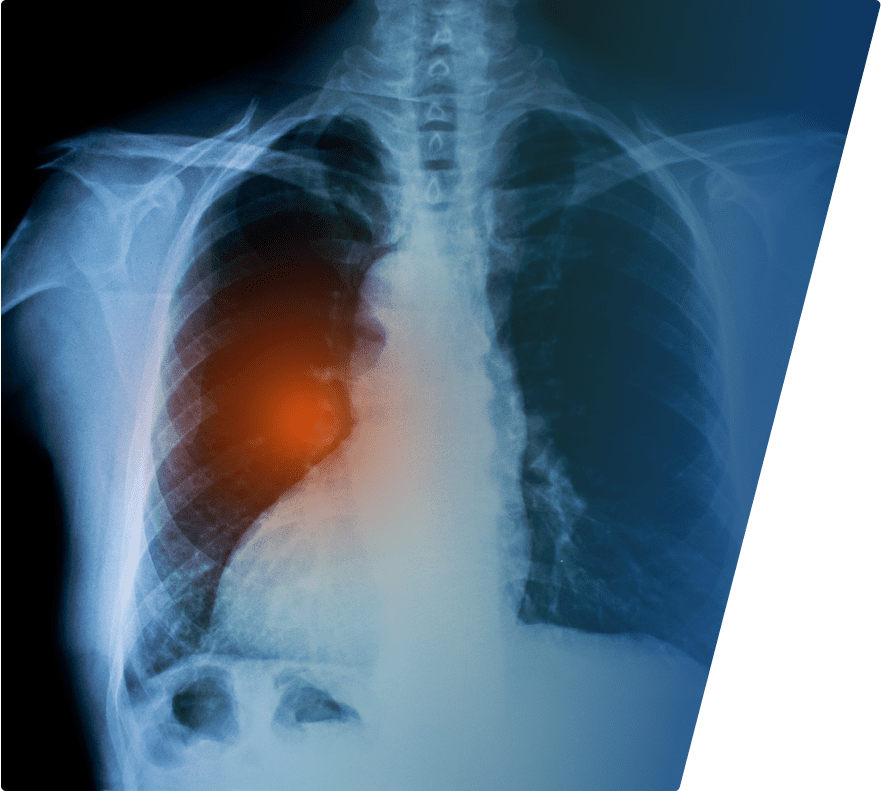

At SWMW Law, we care about your health and want you to get the best medical care available. Mesothelioma is a rare disease, and many top quality hospitals and cancer centers may not have much experience treating this specific cancer.